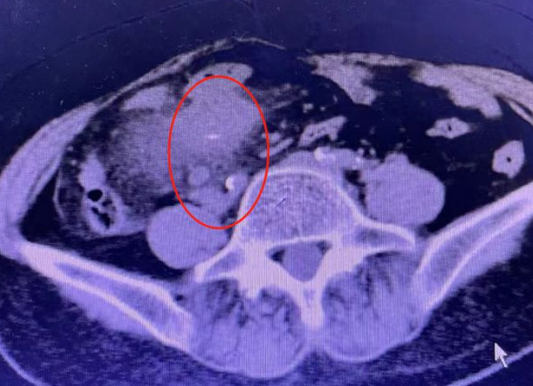

唐成祥醫(yī)生仔細(xì)地閱讀了王大姐之前的CT檢查,在她的右下腹發(fā)現(xiàn)條形的高密度影。這個(gè)高密度影引起了唐成祥醫(yī)生的警覺(jué),高密度影周?chē)哪c管還有輕微的增厚和滲出。經(jīng)過(guò)跟患者的溝通唐成祥醫(yī)生基本判定腹腔里的異物就是魚(yú)刺,且極有可能已經(jīng)扎穿腸壁。如果不抓緊處理,魚(yú)刺鉆出腸道刺破大血管,就要進(jìn)行外科切除小腸手術(shù),隨時(shí)會(huì)有生命危險(xiǎn)。

腹部CT掃描:CT檢查對(duì)腹腔游離氣體的發(fā)現(xiàn)率較高,還能發(fā)現(xiàn)腹腔積液、軟組織腫塊、膿腫、腸壁增厚等征象。氣腹檢出率高達(dá)90%,能夠發(fā)現(xiàn)X線不能發(fā)現(xiàn)的組織間游離氣體。